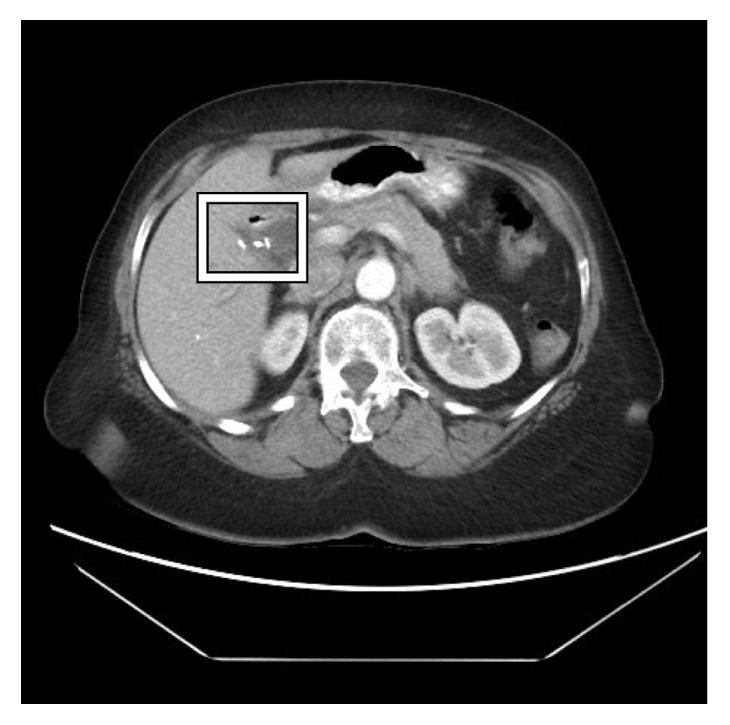

Gallstone disease is a common gastrointestinal pathology that may result in surgical intervention. While cholecystectomy has relatively minimal risks, surgical clip migration is a rare complication that can cause severe morbidity and mortality. This report describes a rare phenomenon of a biliary stone forming onto a migrated surgical clip 14 years after cholecystectomy causing an obstructive jaundice. This case illustrates the importance of keeping a migrated surgical clip on the differential when encountering patients with symptoms of cholangitis after cholecystectomy.

胆结石病是一种常见的胃肠道疾病,可能需要手术干预。虽然胆囊切除术的风险相对较小,但手术夹移位是一种罕见的并发症,可导致严重的发病和死亡。本报告描述了一例罕见现象,即胆囊切除术后14年,一枚移位的手术夹上形成了胆结石,导致梗阻性黄疸。该病例说明了在遇到胆囊切除术后出现胆管炎症状的患者时,将移位的手术夹纳入鉴别诊断的重要性。